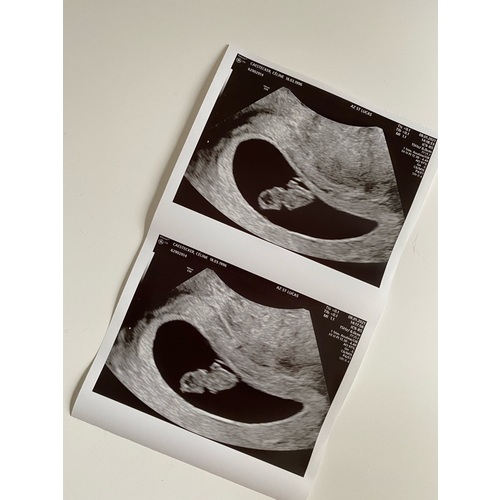

Dit was ons dochtertje met 7+2 weken zwangerschap. Ze was toen 11mm en haar hartje klopte al op een mooi tempo. Veel succes donderdag!